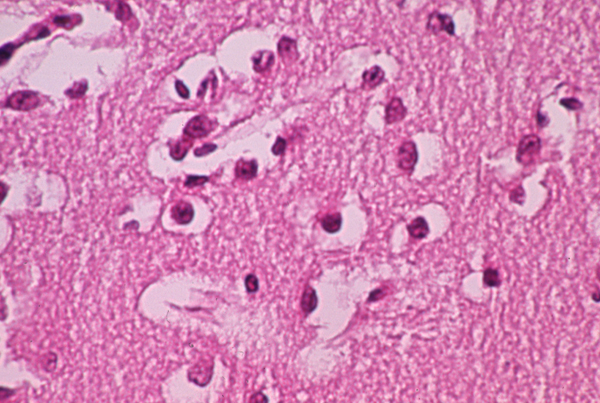

003